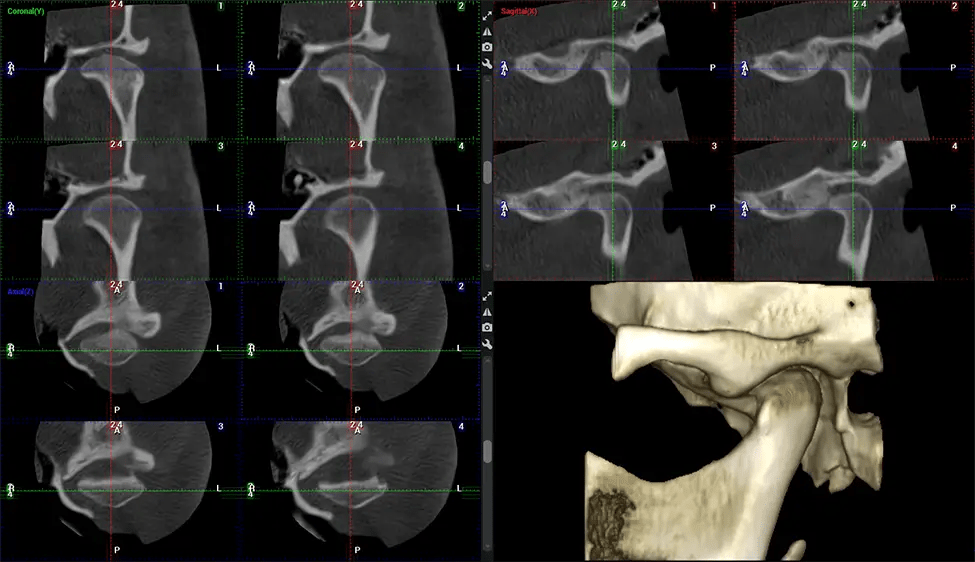

Cone Beam Computed Tomography (CBCT) is an advanced imaging technique used in dentistry and maxillofacial surgery to obtain detailed 3D images of the oral and maxillofacial structures. At Dr G Dental Studio, our CBCT scanners utilize a cone-shaped X-ray beam and a specialized detector to capture images from different angles. A computer then combines these images to create a 3D representation of the patient’s oral anatomy.

This 3D scan, called cone beam computed tomography, gives your dentist a more complete image of your oral anatomy and disease processes than a traditional X-ray. Unlike conventional X-rays, which capture a 2D image of your mouth from various angles, a 3D scan takes multiple digital X-rays for one image. It provides a complete view of your jaw, teeth, nerves, and soft tissues. This enhanced view allows dentists to detect minor issues not visible in traditional 2D scans, such as impacted wisdom teeth or bone fractures in the sinus cavity.

There are many benefits to using CBCT technology, especially compared to the traditional 2D X-ray format. One of the most significant advantages of CBCT scans is that they provide much more information than traditional X-rays. A scan lets your dentist see images from all angles of your jaw and mouth, including your sinuses, nasal cavity, cheekbones, and other surrounding areas. This added information helps your dentist craft a comprehensive treatment plan that addresses all aspects of your oral health.

Another significant benefit is that 3D imaging provides more precise images of your bone structure. These images are more detailed, providing you with a more accurate diagnosis. An accurate diagnosis means better treatment for you.

The patient is first positioned in the CBCT scanner, which typically consists of a rotating arm that houses the X-ray source and a detector. The patient’s head is immobilized to ensure accurate image capture. The X-ray source and detector rotate around the patient’s head, capturing various X-ray images from multiple angles. As the X-ray source rotates, it emits the cone-shaped X-ray beam towards the detector. The detector captures the X-ray images, which are then processed by the CBCT software.

After the scanning process, the captured X-ray images are processed by the CBCT software, which applies algorithms to reconstruct a detailed 3D image of the scanned area. The software compiles these individual X-ray images and creates a digital 3D representation of the patient’s anatomy. The reconstructed 3D CBCT image can be viewed and analyzed by the dentist or radiologist. This image can be manipulated, rotated, and zoomed in or out to examine specific structures and evaluate the patient’s condition.